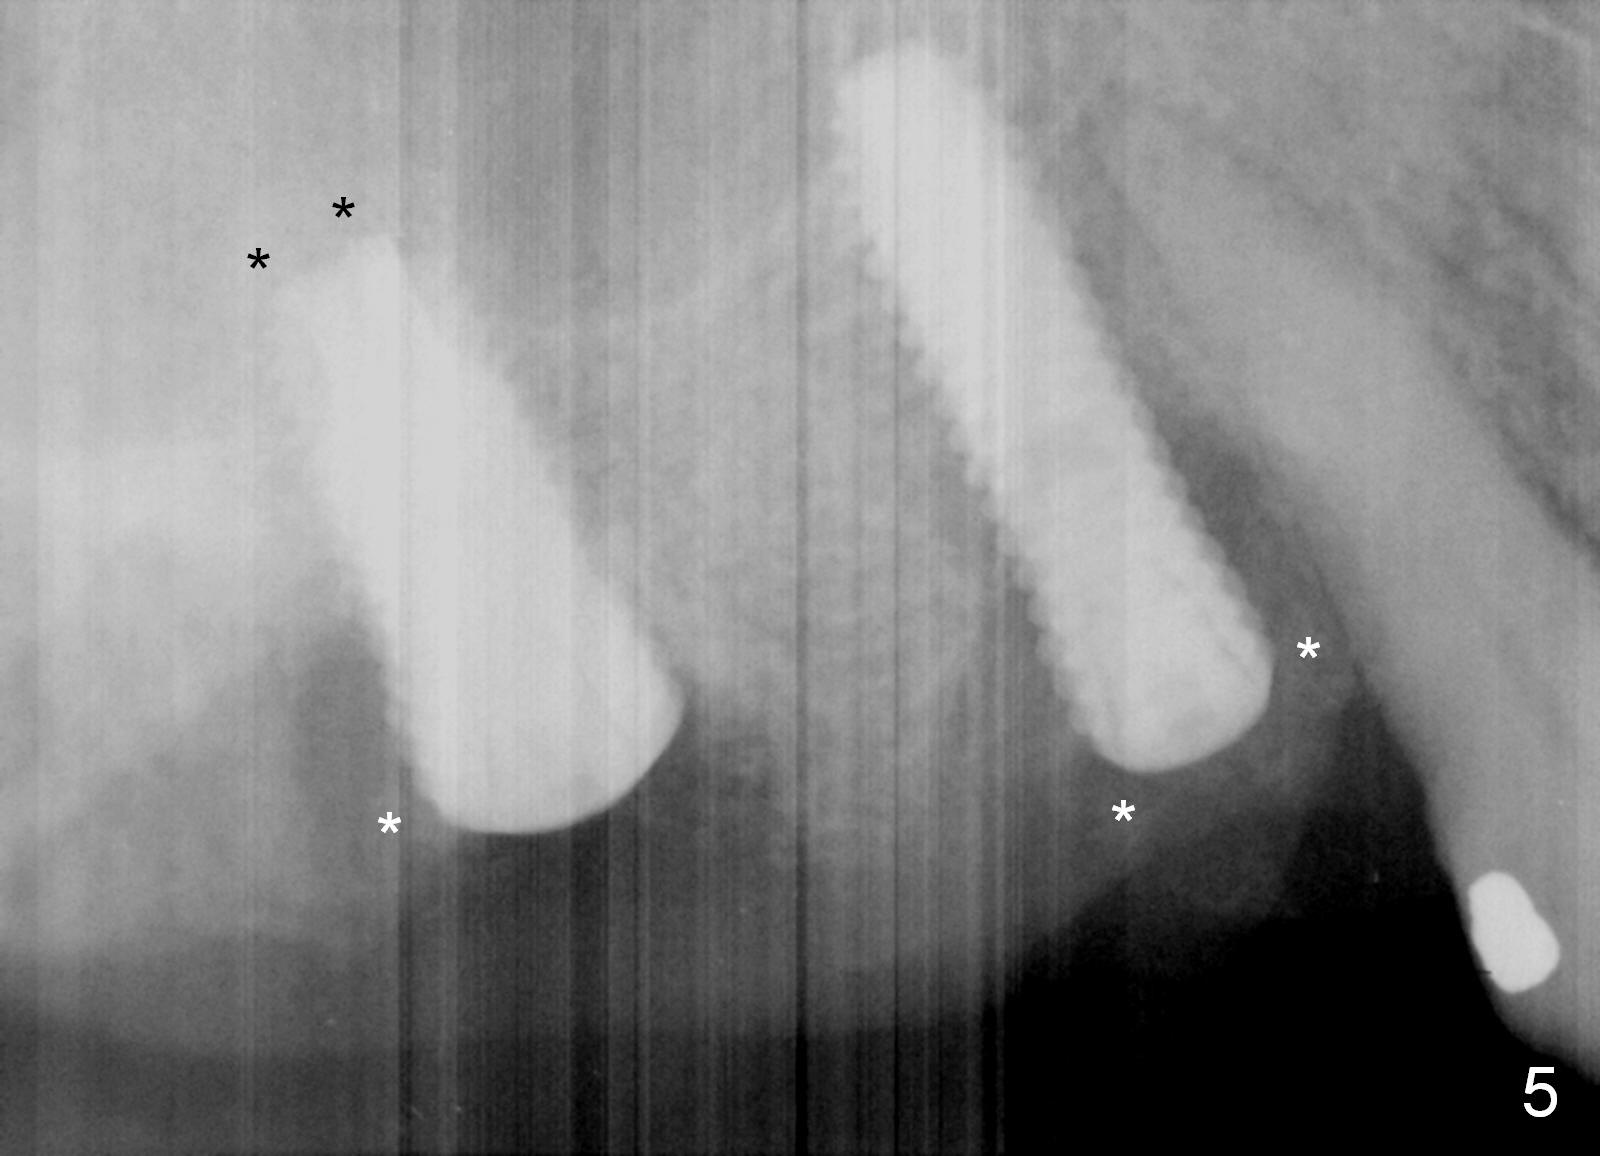

Preop photos show generalized gingival hyperplasia (hypertension med (Amlodipine, Calcium Channel Blocker), Fig.1 *), palatal (Fig.2<) and buccal (Fig.3 B) abscesses originated from the tooth #5. There is a smaller abscess buccal to the tooth #3 (not shown). After extraction, the buccal and palatal plates of the teeth #3 and 5 are found basically non-existent. When taps are placed, large socket defects are evident (Fig.4 *). In addition to sinus lift at #3 (Fig.5 black *), mineralized cancellous and cortical allograft (.5-1 and 1-2 mm) is placed around the implants with healing screws in place (white *). After the healing screws are removed and cemented abutments are placed, more allograft is packed (Fig.6-8 *). Closing the "dead" space in step may prevent immediately postop infection and peri-implantitis.